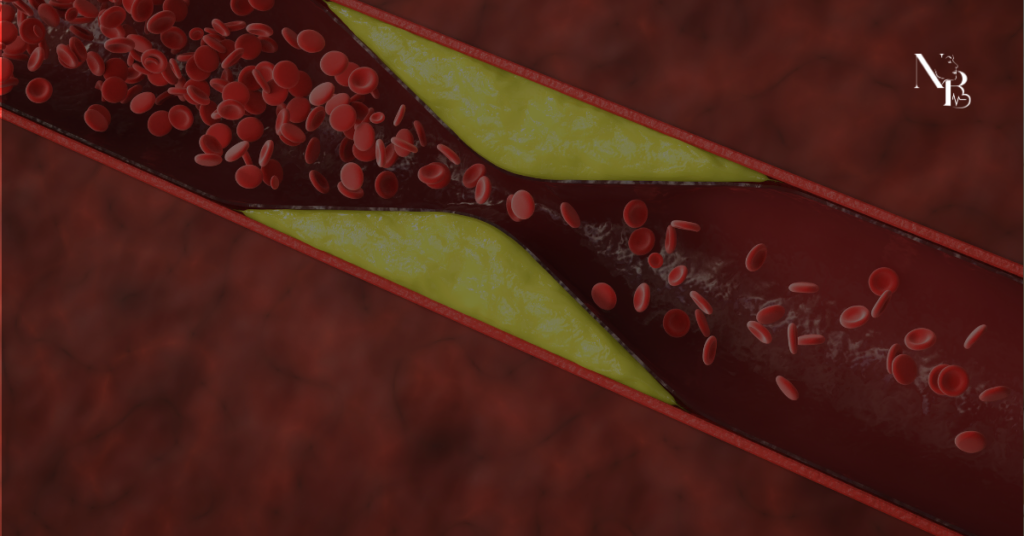

A obesidade é um importante fator de risco para o desenvolvimento de doenças cardíacas e está diretamente relacionada a alterações que sobrecarregam o coração. O excesso de gordura corporal, especialmente na região abdominal, pode provocar inflamações, alterações metabólicas e aumento da pressão arterial, contribuindo para problemas cardiovasculares. Neste conteúdo, explicamos a relação entre obesidade e saúde do coração, destacando a importância da prevenção, do acompanhamento médico e de hábitos saudáveis para reduzir riscos e proteger a saúde cardiovascular.

O infarto é uma condição grave que exige atenção imediata. Saiba identificar os sintomas do ataque cardíaco, fatores de risco e medidas eficazes de prevenção com orientação do Dr. Bruno Bacelar, cardiologista em Brasília.